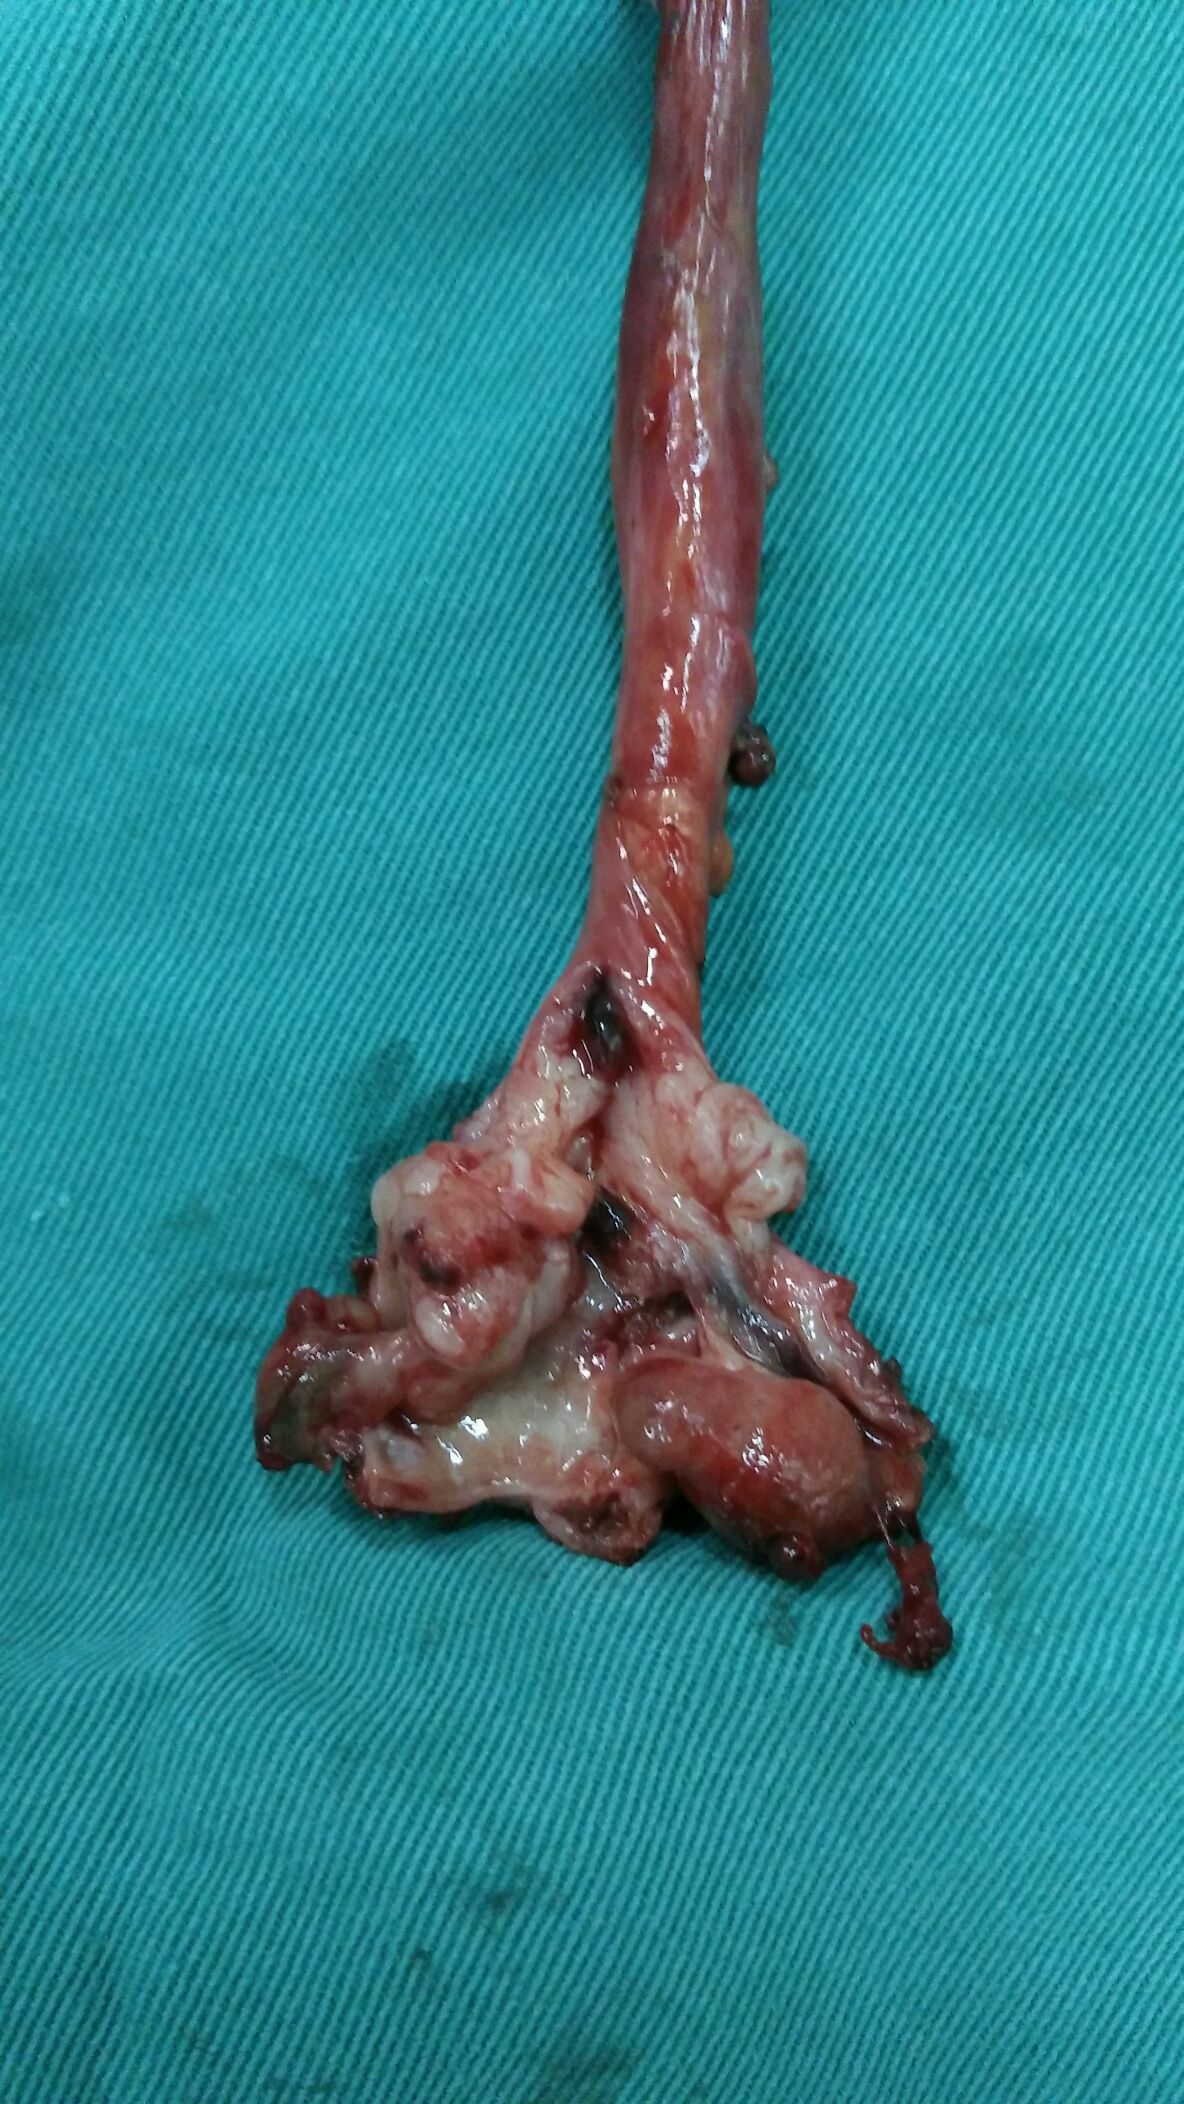

经腹腔镜完成的输尿管癌根治术标本.

标本剖开后,显示肿瘤(输尿管癌), 积水外溢,管径变细

输尿管下段尿路上皮癌(大体)